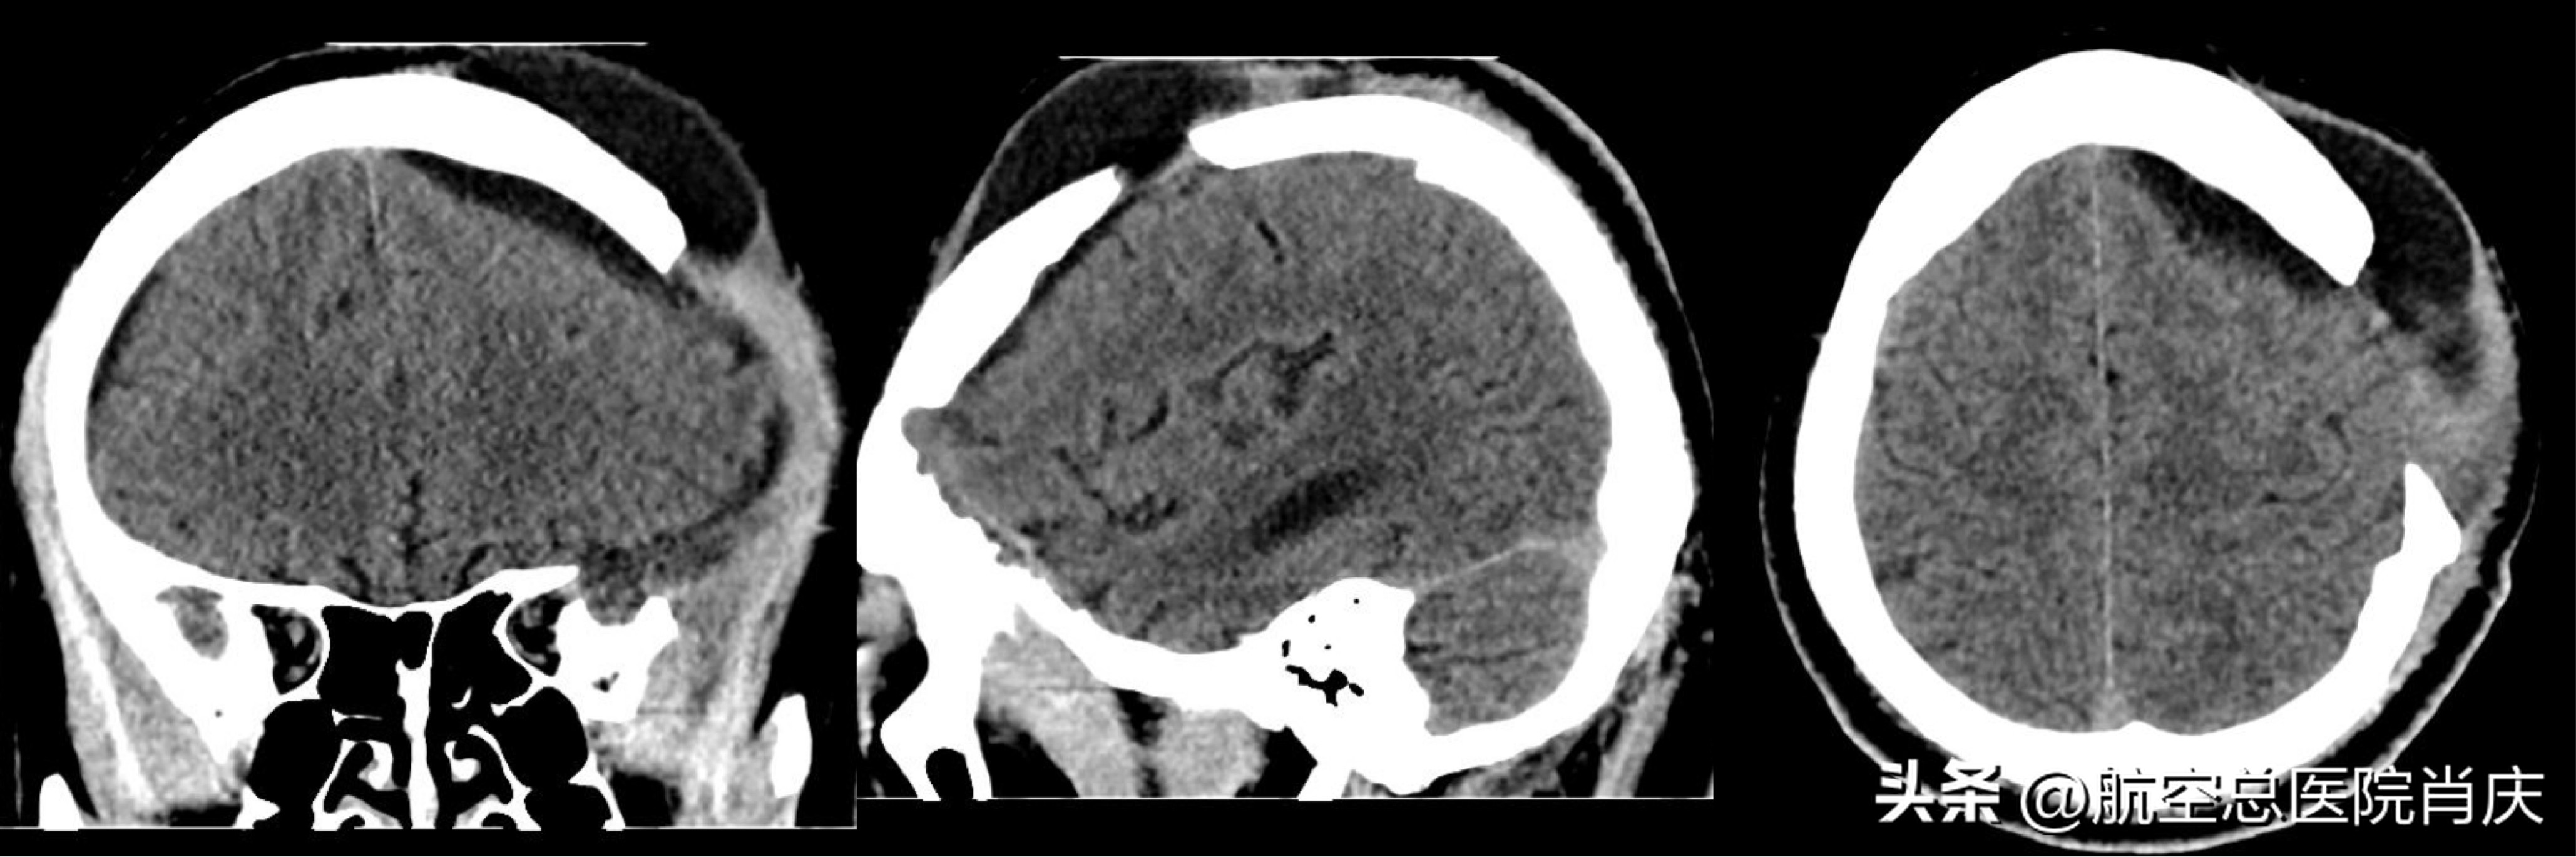

术前

常某脑外伤术后持续高热,病情危急,入院后完善各项检查的同时进行抗感染及保肝治疗。根据头颅影像学检查及患者体征明确诊断,曾开放性颅脑损伤,去骨瓣减压术后,仍存在皮下积液及体温升高,需清除局部脓苔,并结合抗感染治疗。确定了治疗方案,肖主任团队为常某在全麻下行硬膜外脓肿清除术。手术非常顺利成功,术后继续抗感染对症治疗。历时18天的医治,患者常某恢复良好,不再有发热、头痛的症状,可以正常交流,起身,行走,已经可以出院休养。